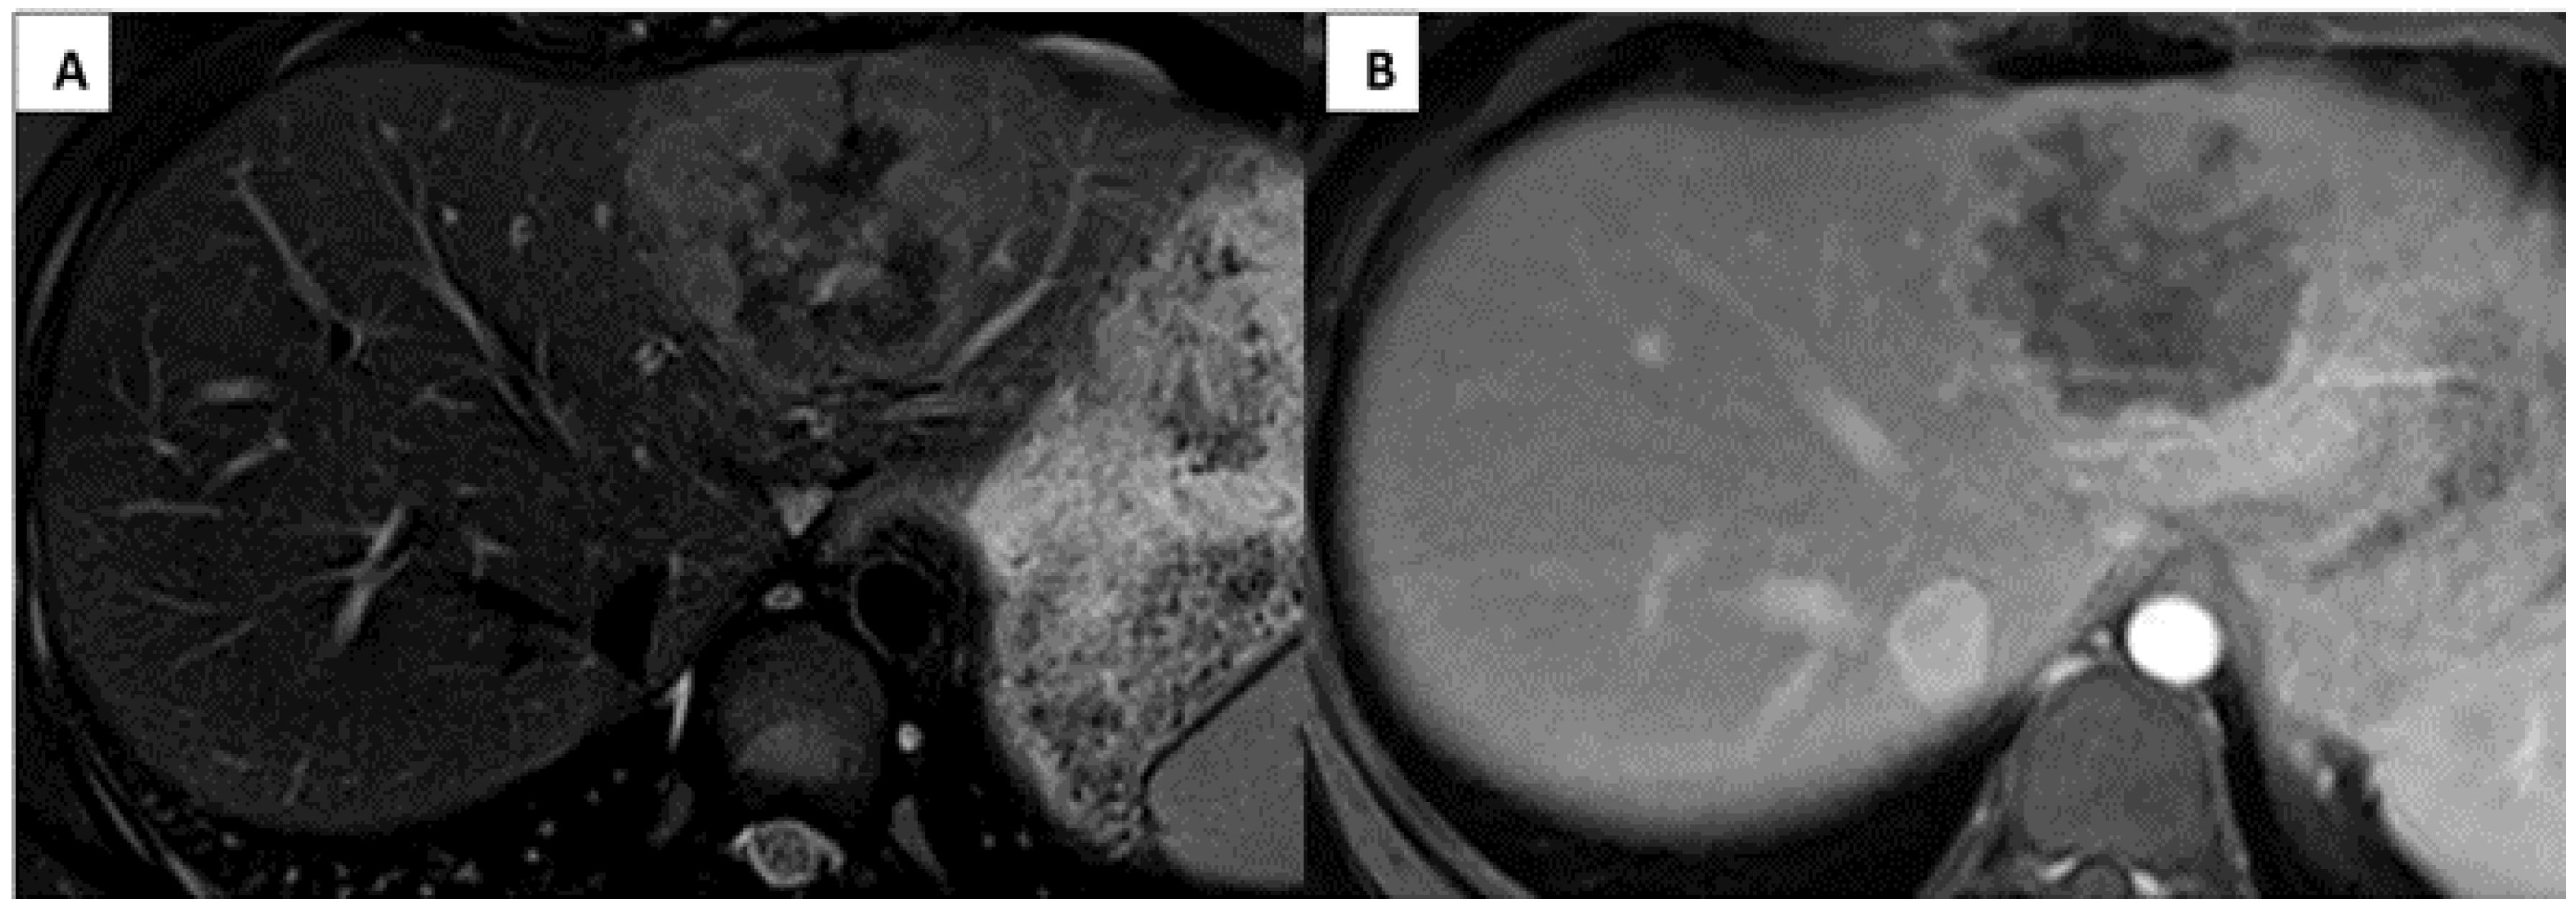

An abdominal computerized tomography (CT) scan with contrast showed a 6.2 × 4.8 cm tumor involving the left liver, including segments II, III, and IVa. MRI of the abdomen with gadoxetate disodium (EovistTM or PrimovistTM) showed a unifocal left hepatic lesion with lobular peripheral enhancement, suspicious for FL-HCC (Figure 1).

Figure 1. Imaging appearance of fibrolamellar hepatocellular carcinoma. Axial MRI liver demonstrates the PRETEXT II single left hepatic mass in segments II, III, and IVa with mild peripheral hyperintensity and central hypointensity on T2 fat saturation images (A) and iso to hypointensity on the post contrast phase (B).